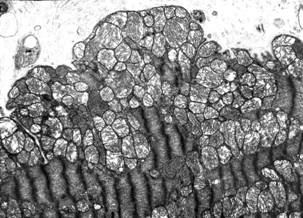

Перемещение митохондрий в кардиомиоците левого желудочка крысы после воздействия ИЗП (Погодина и соавторы, 2006)

Митохондрии играют ключевую роль на начальных стадиях развития апоптоза, поэтому изменения в их структуре является важным морфологическим критерием апоптоза кардиомиоцитов. В работе Погодиной Л.С. и соавторов отмечалось просветление матрикса митохондрий с редукцией крист (наиболее выраженное у кардиомиоцитов С типа), также вытеснение митохондрий из центральных участков клетки на периферию, где они скапливались в многочисленных выступах саркоплазмы («почках») [6].

Михайлов В.М. и соавторы также наблюдали уменьшение электронной плотности митохондрий, к тому же были выявлены митохондрии, содержащие овальные включения (кальций-фосфатной природы), что свидетельствовало о том, что гибель кардиомиоцитов происходила не по типу острого ишемического некроза (для начальной, обратимой стадии которого характерно появление игольчатых включений) [4].

При индукции апоптоза кардиомиоцитов в условиях аноксии Сапрунова В.Б. и соавторы наблюдали гетерогенность популяции митохондрий: основную массу составляли митохондрии с обводнённым, просветлённым матриксом, контрастными мембранами, меньшее количество митохондрий характеризовалось сжатым, уплотнённым матриксом. При продолжительном действии аноксии впервые были выявлены локальные перестройки внутренней мембраны митохондрий с образованием ячеистых упорядоченных структур и необычное расположение мелких электронно-плотных митохондрий внутри более крупных с просветлённым матриксом [3].